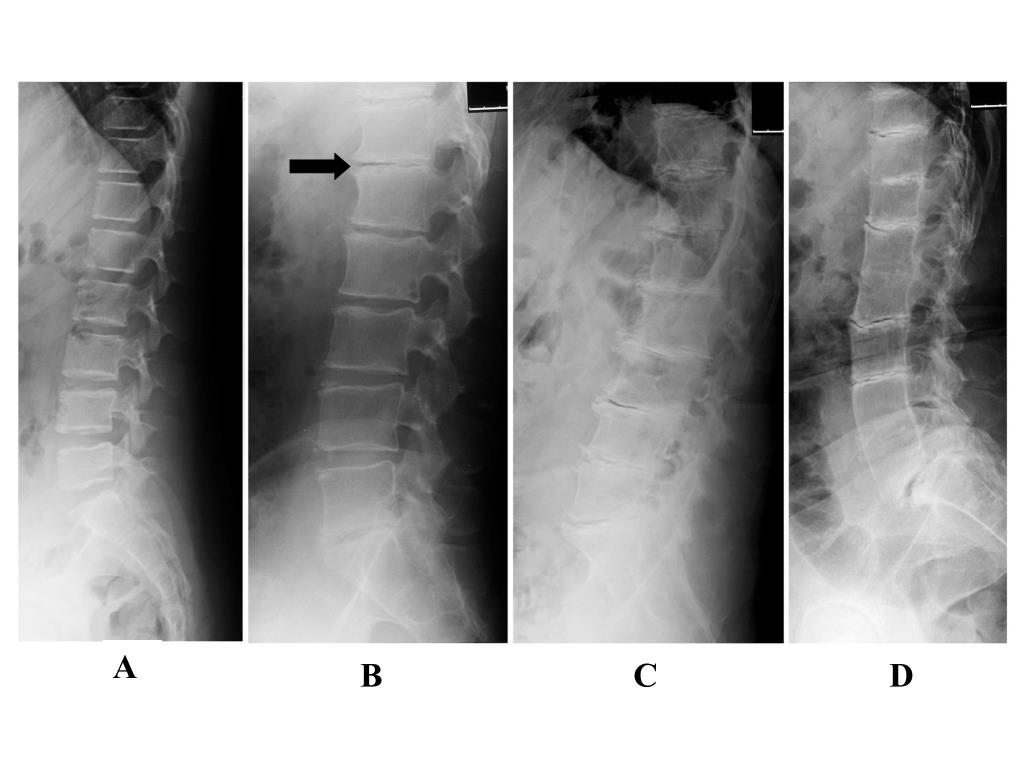

31. A B C D

32. 55 y 64y Age(y) Age(y) % of patients not manifesting Joint replacement Renal stones 54 y 59 y Age(y) Age(y) Cardiac valve involvement Coronary artery calcification